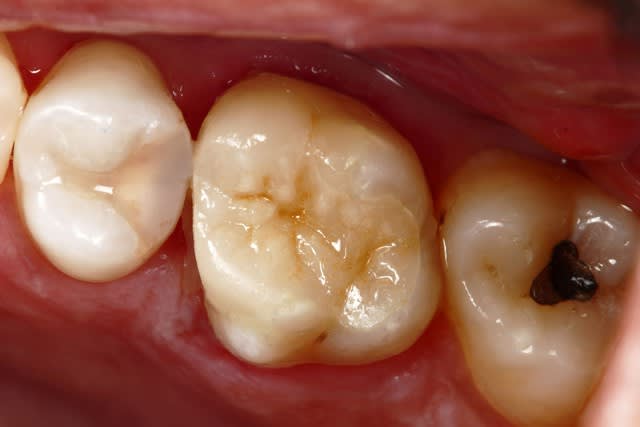

Ensuite le cas parait plus simple bien sur Marc ;) mais en fait tout découle de la prise de décision initiale de préserver et coller...

Onlay Emax. Tout est dans l'émail a part la limite mesiale, le risque de carie est plus faible, le risque de contamination de l'endodonte plus faible aussi...

Mécaniquement ça me parait un meilleur choix que la couronne avec inlay core...

mais après tout c'est surement dans ma tête ;)